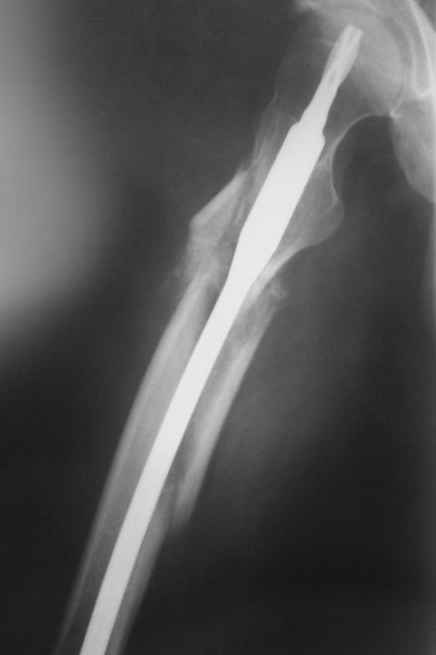

по поводу бедра - все сделано правильно, есть прекрасная апозиция основных фрагментов почти на всем диаметре перелома, в этом районе прекрасное кровоснабжение и нет никакого смысла гончяться за осколком

Практически единственное, что делает необходимым разрез для манипуляций с промежуточным отломком бедренной кости - это его "застегивание" в илиотибиальном тракте по типу пуговицы в петле.

Когда при движениях в колене этот отломок на сантиметры смещается, создавая очевидный дискомфорт. Даже в этом случае репозиция отломка

именно в его ложе избыточна, достаточно осциллирующей пилой отсечь то, что выстоит над фасцией.

Отломок, расположенный так, как на показанных рентгенограммах бедра, обычно на снимках в 1-2 мес. уже располагается ближе к диафизу и

включается в мозоль.

То есть в представленных ситуациях при штифтовании ни на бедре, ни на голени не нужно делать ни открытую, ни закрытую (с помощью шильев,

спиц, еще каких-то "джойстиков") репозицию. Все, что нужно - восстановить ось, длину и ротацию.